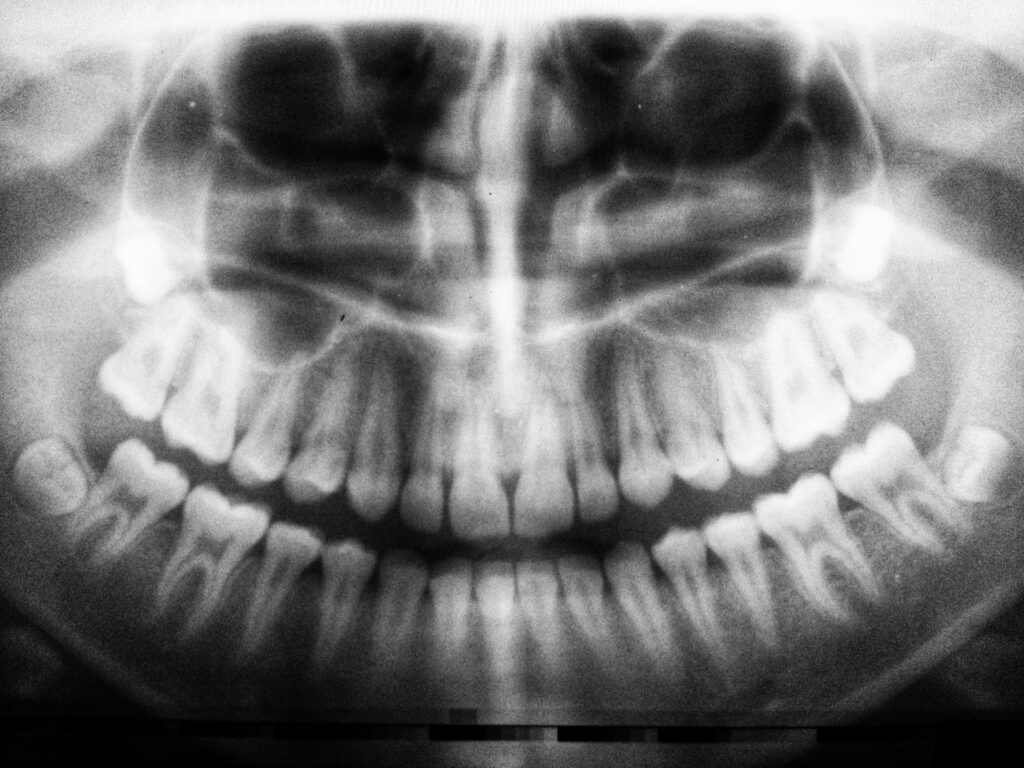

Gnatometria to dział diagnostyki stomatologicznej, który zajmuje się pomiarami oraz analizą ruchów żuchwy, relacji zwarciowych i pracy stawów skroniowo-żuchwowych. Metoda ta pozwala ocenić funkcjonowanie układu stomatognatycznego, a jednocześnie wspiera planowane leczenie protetyczne Kraków, ortodontyczne i implantologiczne. Dzięki gnatometrii stomatolog może dokładnie zrozumieć przyczyny dolegliwości oraz zaplanować skuteczny zabieg.

Gnatometria odgrywa kluczową rolę w nowoczesnej stomatologii, ponieważ umożliwia precyzyjną ocenę zwarcia i ruchów żuchwy. W klinice stomatologicznej badanie to stosuje się zarówno u pacjentów z bólem stawów skroniowo-żuchwowych, jak i u osób przygotowywanych do leczenia protetycznego lub implantów. Co więcej, analiza gnatometryczna pomaga zapobiegać przeciążeniom zębów oraz nawrotom dolegliwości po zakończonym leczeniu.

Badanie gnatometryczne przeprowadza się w kontrolowanych warunkach klinicznych. Stomatolog wykorzystuje specjalistyczne urządzenia pomiarowe, które rejestrują ruchy żuchwy oraz siły zwarcia. Cały proces jest nieinwazyjny, szybki i komfortowy dla pacjenta, a jednocześnie dostarcza dokładnych danych diagnostycznych. Uzyskane wyniki pozwalają dopasować leczenie do indywidualnych potrzeb pacjenta.